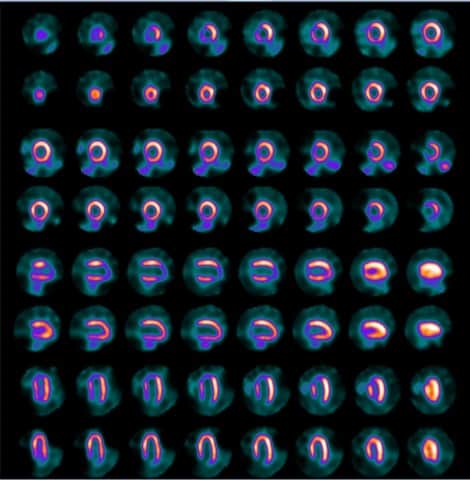

Imagistica perfuziei miocardice 4 min stres / 6 min repaus